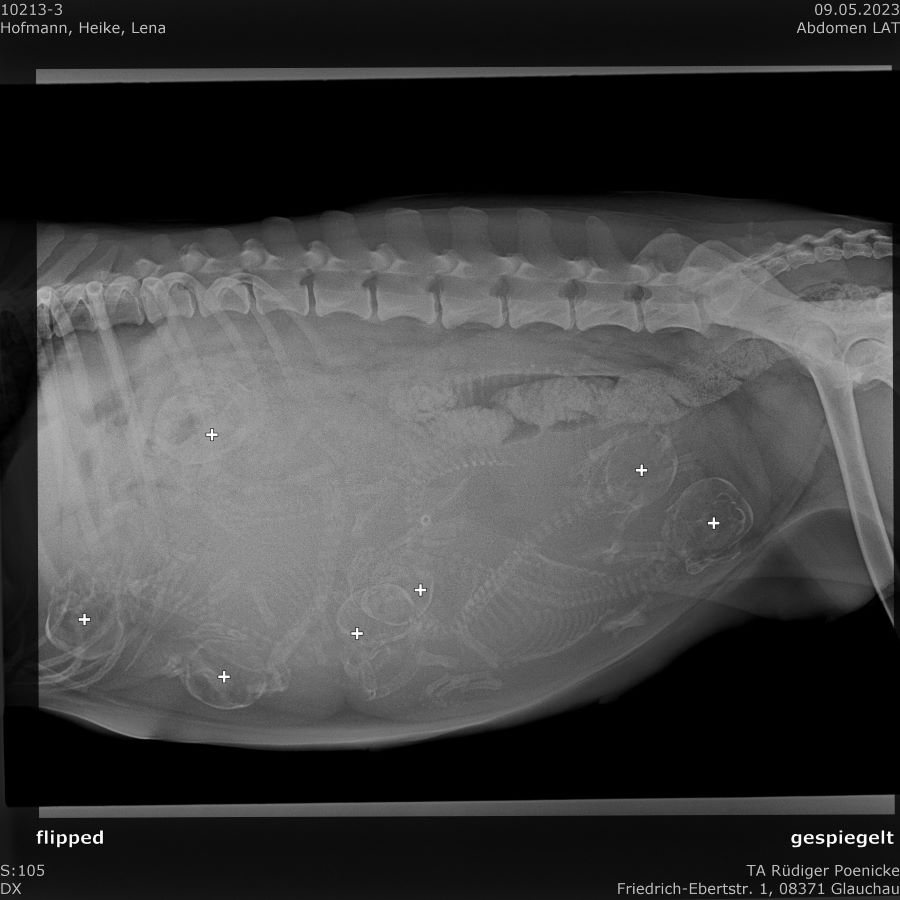

09.05.2023

Heute war ich mit Lena beim Röntgen.

Es wurden sieben Welpen gezählt.

Zwei mehr, als beim Ultraschall. :)

Die Spannung und Aufregung wächst.

Es sind nur noch wenige Tage.

Juhu...